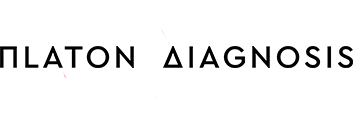

Η ελαστογραφία κατέγραψε με ακρίβεια την περιοχή αυξημένης σκληρότητας (κόκκινο χρώμα) που έγινε αντιληπτή ψηλαφητικά από την ίδια την γυναίκα κατά τη διάρκεια αυτοεξέτασης των μαστών της. Με αυτό τον τρόπο κατέστη δυνατή η στοχευμένη και με ακρίβεια λήψη υλικού κατά τη διενεργηθείσα βιοψία.